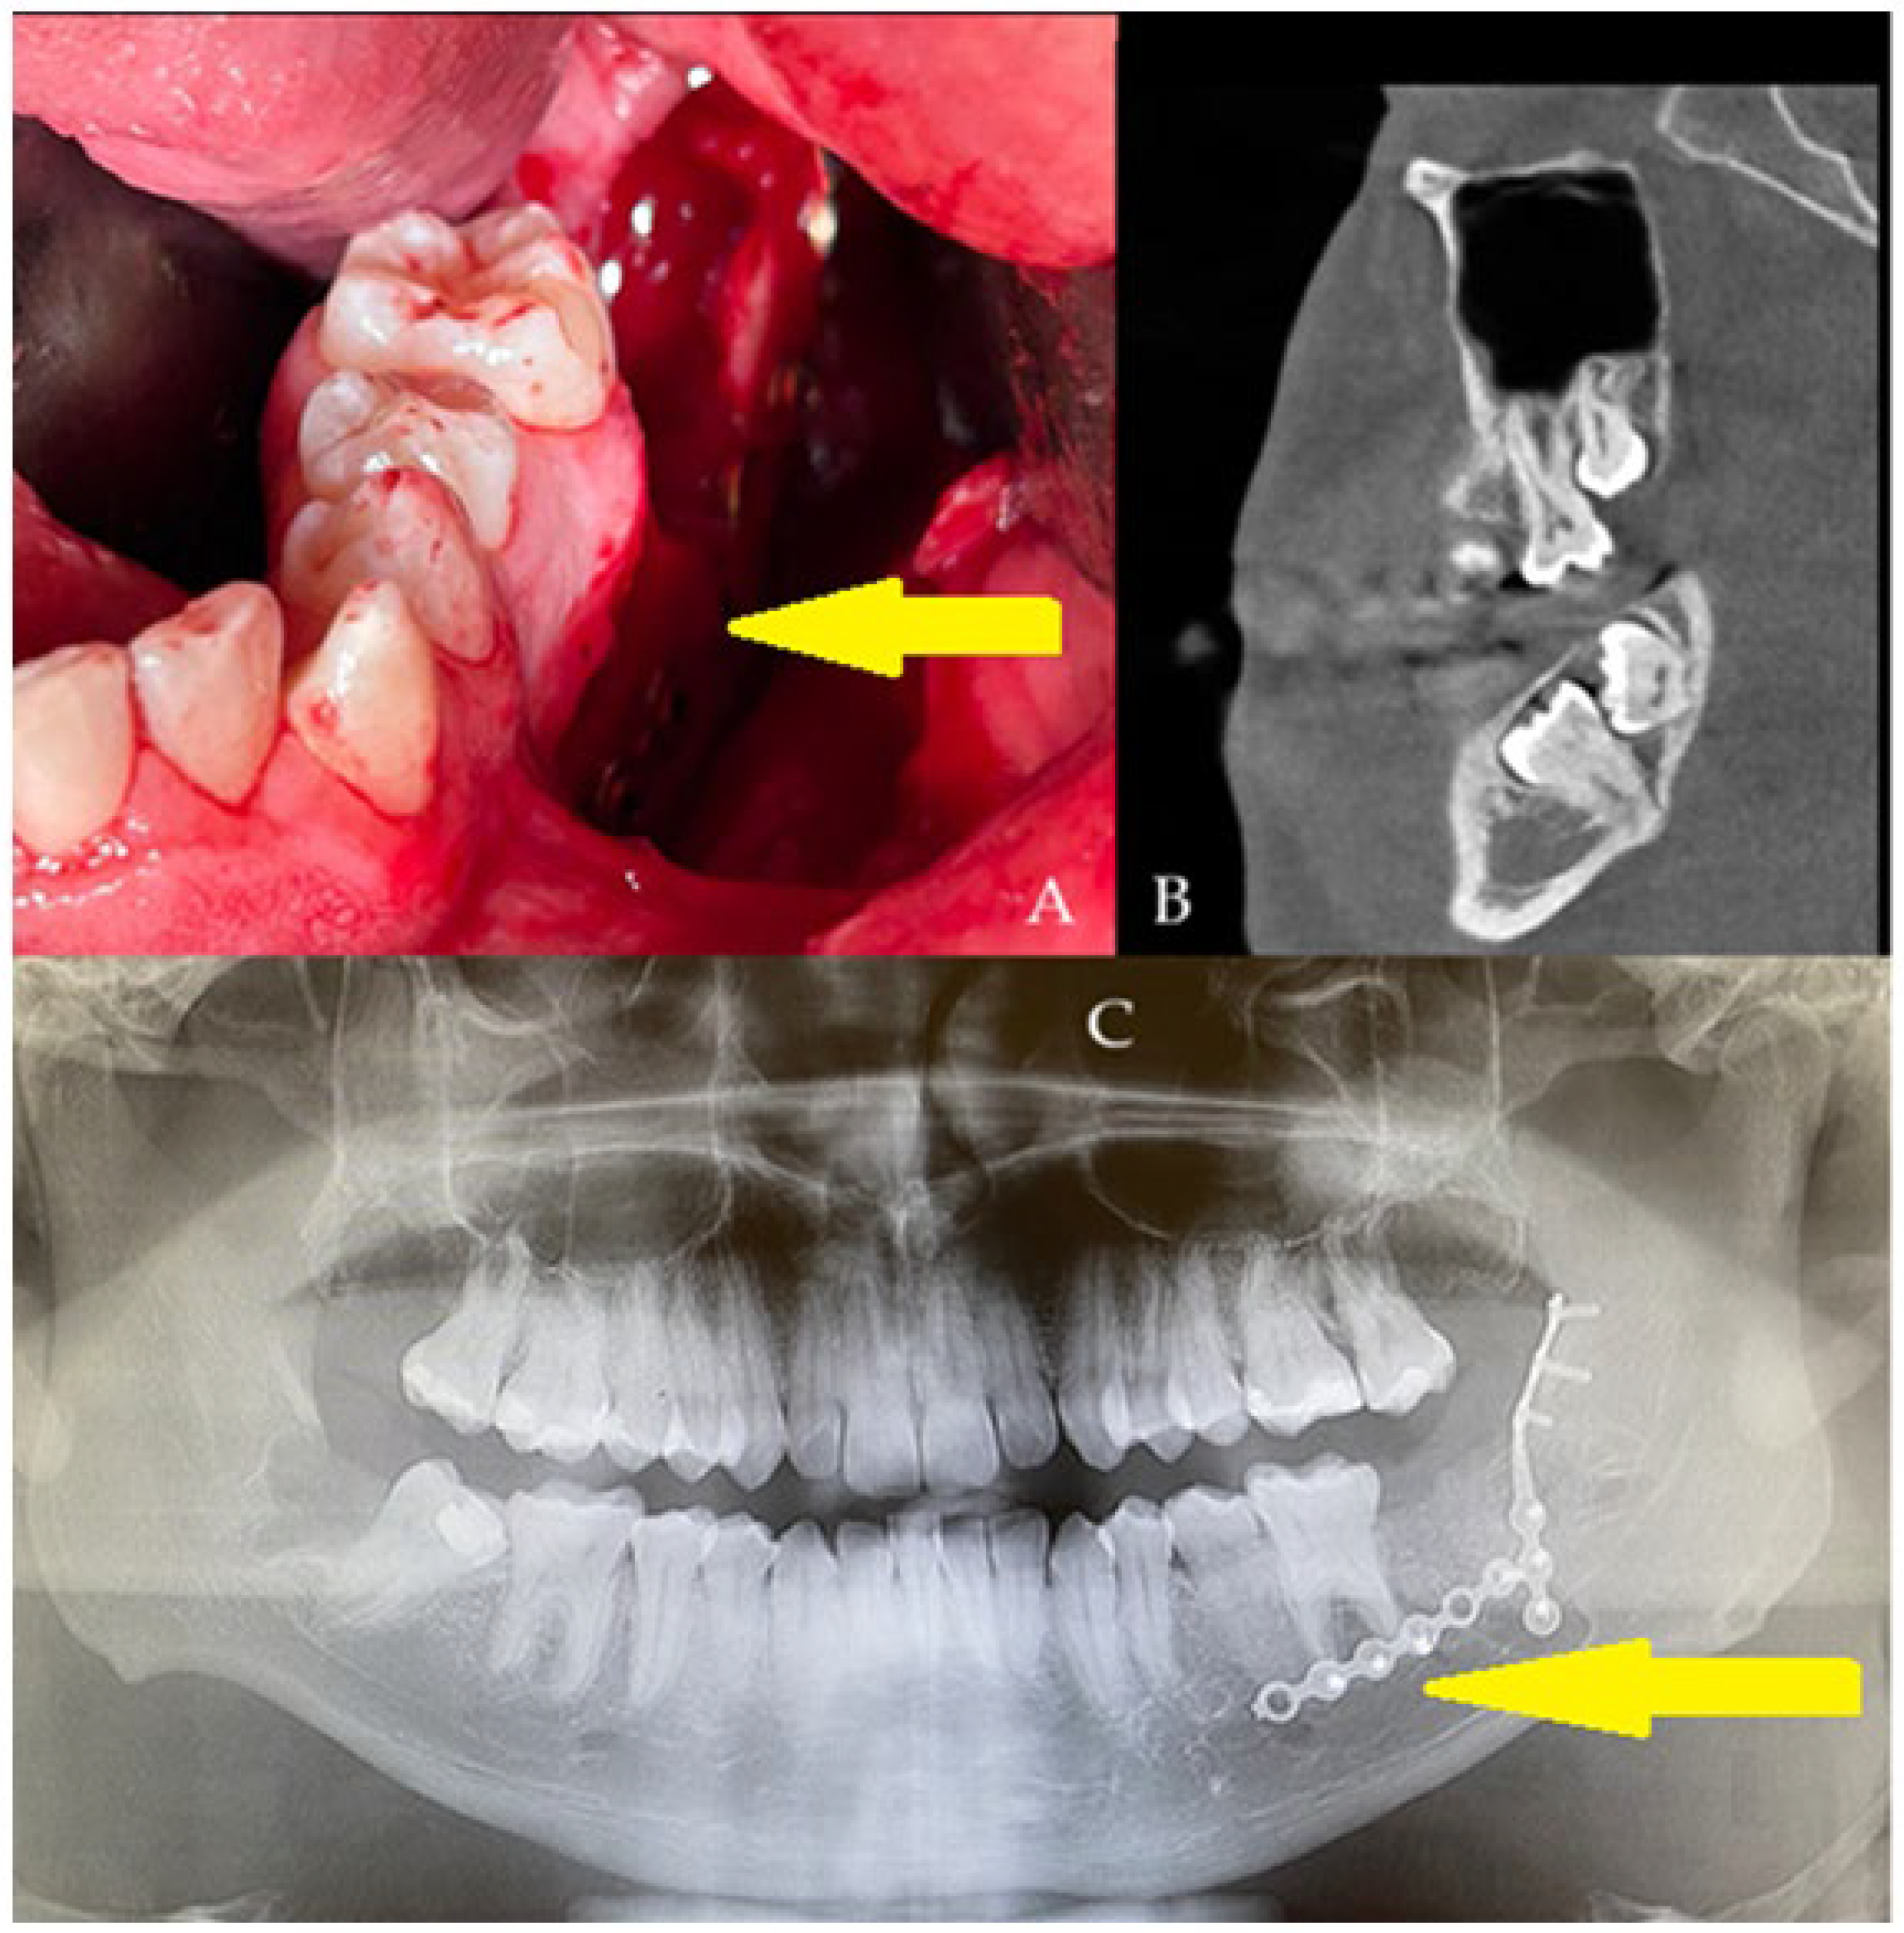

A generally healthy 20-year-old male was scheduled for surgery under general anesthesia and nasotracheal intubation. The oral cavity was free of the intubation tube, which was sutured to the nares, just in case of any mandibular fracture, the necessity of setting proper occlusion or applying additional devices, if they would be necessary. All wisdom teeth 18, 28, 48, with impacted 37, 38 ((B), sagittal view) were removed for orthodontic purposes and scheduled treatment of malocclusion. Typical surgical tooth removal was uneventful; however, because of slight bending of both cortical plates, additional titanium plates were used (yellow arrow, (C)) (2.0 System, Medartis, Basel, Switzerland). To improve PMP outcomes, an additional 10 cm3 allogeneic bone graft (FFABG, fresh–frozen allogeneic bone graft, RCKiK, Katowice, Poland) was placed in the bone deficit to improve the healing period, and then a layer-by-layer suture technique for both lingual and buccal flaps was used to cover the deficit tightly (A). In the first seven days, a postoperative panx revealed a very good titanium plate position, along with a stable bone graft position not exceeding the alveolar ridge. After two weeks, a slight wound dehiscence just behind tooth 36 was noted. Local treatment of the wound and its debridement was not scheduled because the patient denied any revision or local surgery protocol. The wound decreased in size over time. The patient was clear of inflammation and pus formation, and no more bone was visible; a slight wound was left for secondary healing. The allogeneic bone graft requires very careful usage, improved oral hygiene, and very gentle wound care [4,5].